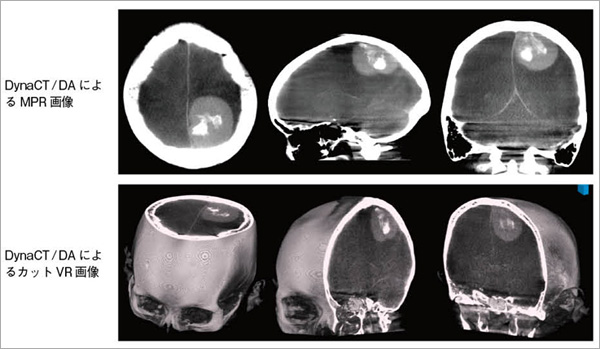

図3 頸動脈ステント(留置後)